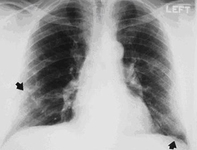

Asbestosis

Posterior-anterior view of the chest with "en face" pleural changes in the mid zones on the right and left (arrows)

From the personal collection of Kenneth D. Rosenman MD